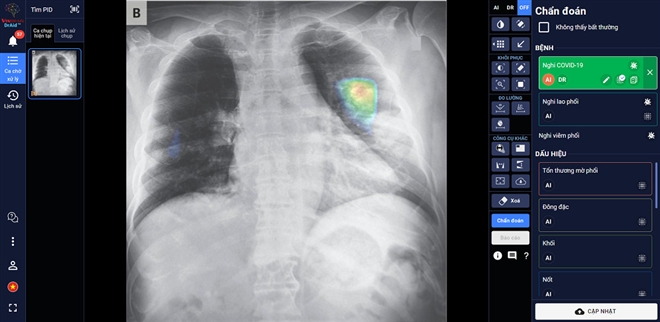

Bác sĩ sử dụng DrAid™ trong chẩn đoán hình ảnh.

DrAid™ – phần mềm AI trợ lý bác sĩ đầu tiên tại Việt Nam - do các chuyên gia, nhà khoa học của VinBrain (công ty công nghệ thuộc Tập đoàn Vingroup) nghiên cứu phát triển thành công. DrAid hiện có khả năng hỗ trợ chẩn đoán 20 dấu hiệu bất thường và bệnh lý về tim - phổi - xương với độ chính xác trên 88% trong vòng 5 giây, đồng thời tự động đưa ra báo cáo y tế theo chuẩn quốc tế JCI có khoanh vùng và đo kích thước chính xác tại khu vực bất thường.

Đặc biệt, DrAid™ mang lại 4 giá trị ưu việt trong phát hiện và điều trị COVID-19 dựa trên ảnh X- quang ngực thẳng gồm: Phát hiện nhanh góp phần sàng lọc mầm bệnh trong cộng đồng, song song cùng phương pháp xét nghiệm PCR. Kết hợp cùng xét nghiệm PCR từ đó nâng cao độ chính xác, giảm thiểu tình trạng âm tính giả tránh bỏ sót; Hỗ trợ đánh giá tiên lượng tình trạng bệnh nhân thông qua lịch sử hình ảnh chụp X-quang, để từ đó có hướng điều trị phù hợp; Hỗ trợ tăng tính nhất quán và chuyển giao kiến thức của bác sĩ từ tuyến Trung ương tới cơ sở.

DrAid™ chẩn đoán và tiên lượng điều trị bệnh nhân COVID-19 dựa trên hình ảnh X-quang ngực thẳng.